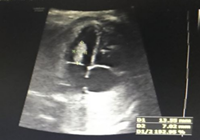

近日,苏州市立医院本部超声科接到了一个会诊请求,胎儿心脏肿瘤,旁人听了都觉得不可思议,怎么还在妈妈肚子中的胎儿心脏会有肿瘤了呢?

小果(化名)是一个孕妈妈,像所有准妈妈一样期待着宝宝的降临,一日,她轻托着隆起的腹部去做超声检查,静静的躺在B超床上,看着医生拿着检查探头在大肚子划来划去,然后医生告诉她胎儿在心脏那里好像有异常的回声,说要转诊到苏州市立医院本部去再检查检查。当时小果只当是小医院技术不行,然后就来到了市立医院本部。

像往常一样,她很配合医生检查,只见医生突然把检查探头停在了肚子的一个地方,就在那个地方检查来检查去,她感觉不是很好,忙问:“医生,怎么了?我的宝宝是不是有什么问题?”,她表现得很是焦急。医生说:“宝宝的心脏长了个肿瘤”。她当时都吓蒙了,觉得怎么会呢?胎儿心脏也会有肿瘤?可是这么大的事情,医生也不可能跟她开玩笑呀,她一时没缓过神来。说起肿瘤,可能大家往往想到的都是中老年人,尽管现在肿瘤越来越年轻化,可是年轻到胎儿,还真是令人吃惊。

市立医院本部超声中心胎儿心超室潘琦医生介绍,胎儿心脏肿瘤在心脏疾病中极为少见,但胎儿期心脏肿瘤相对常见,其发生率约为1/10000,绝大多数为良性,其中最常见的是横纹肌瘤,约占心脏肿瘤的50%以上,其次是畸胎瘤,纤维瘤等,50%以上的心脏横纹肌瘤伴有结节性硬化,多发者伴有结节性硬化的可能性更高,因此,产前检查发现胎儿心脏肿瘤后应建议孕妇接受优生优育咨询和相关遗传学检查。